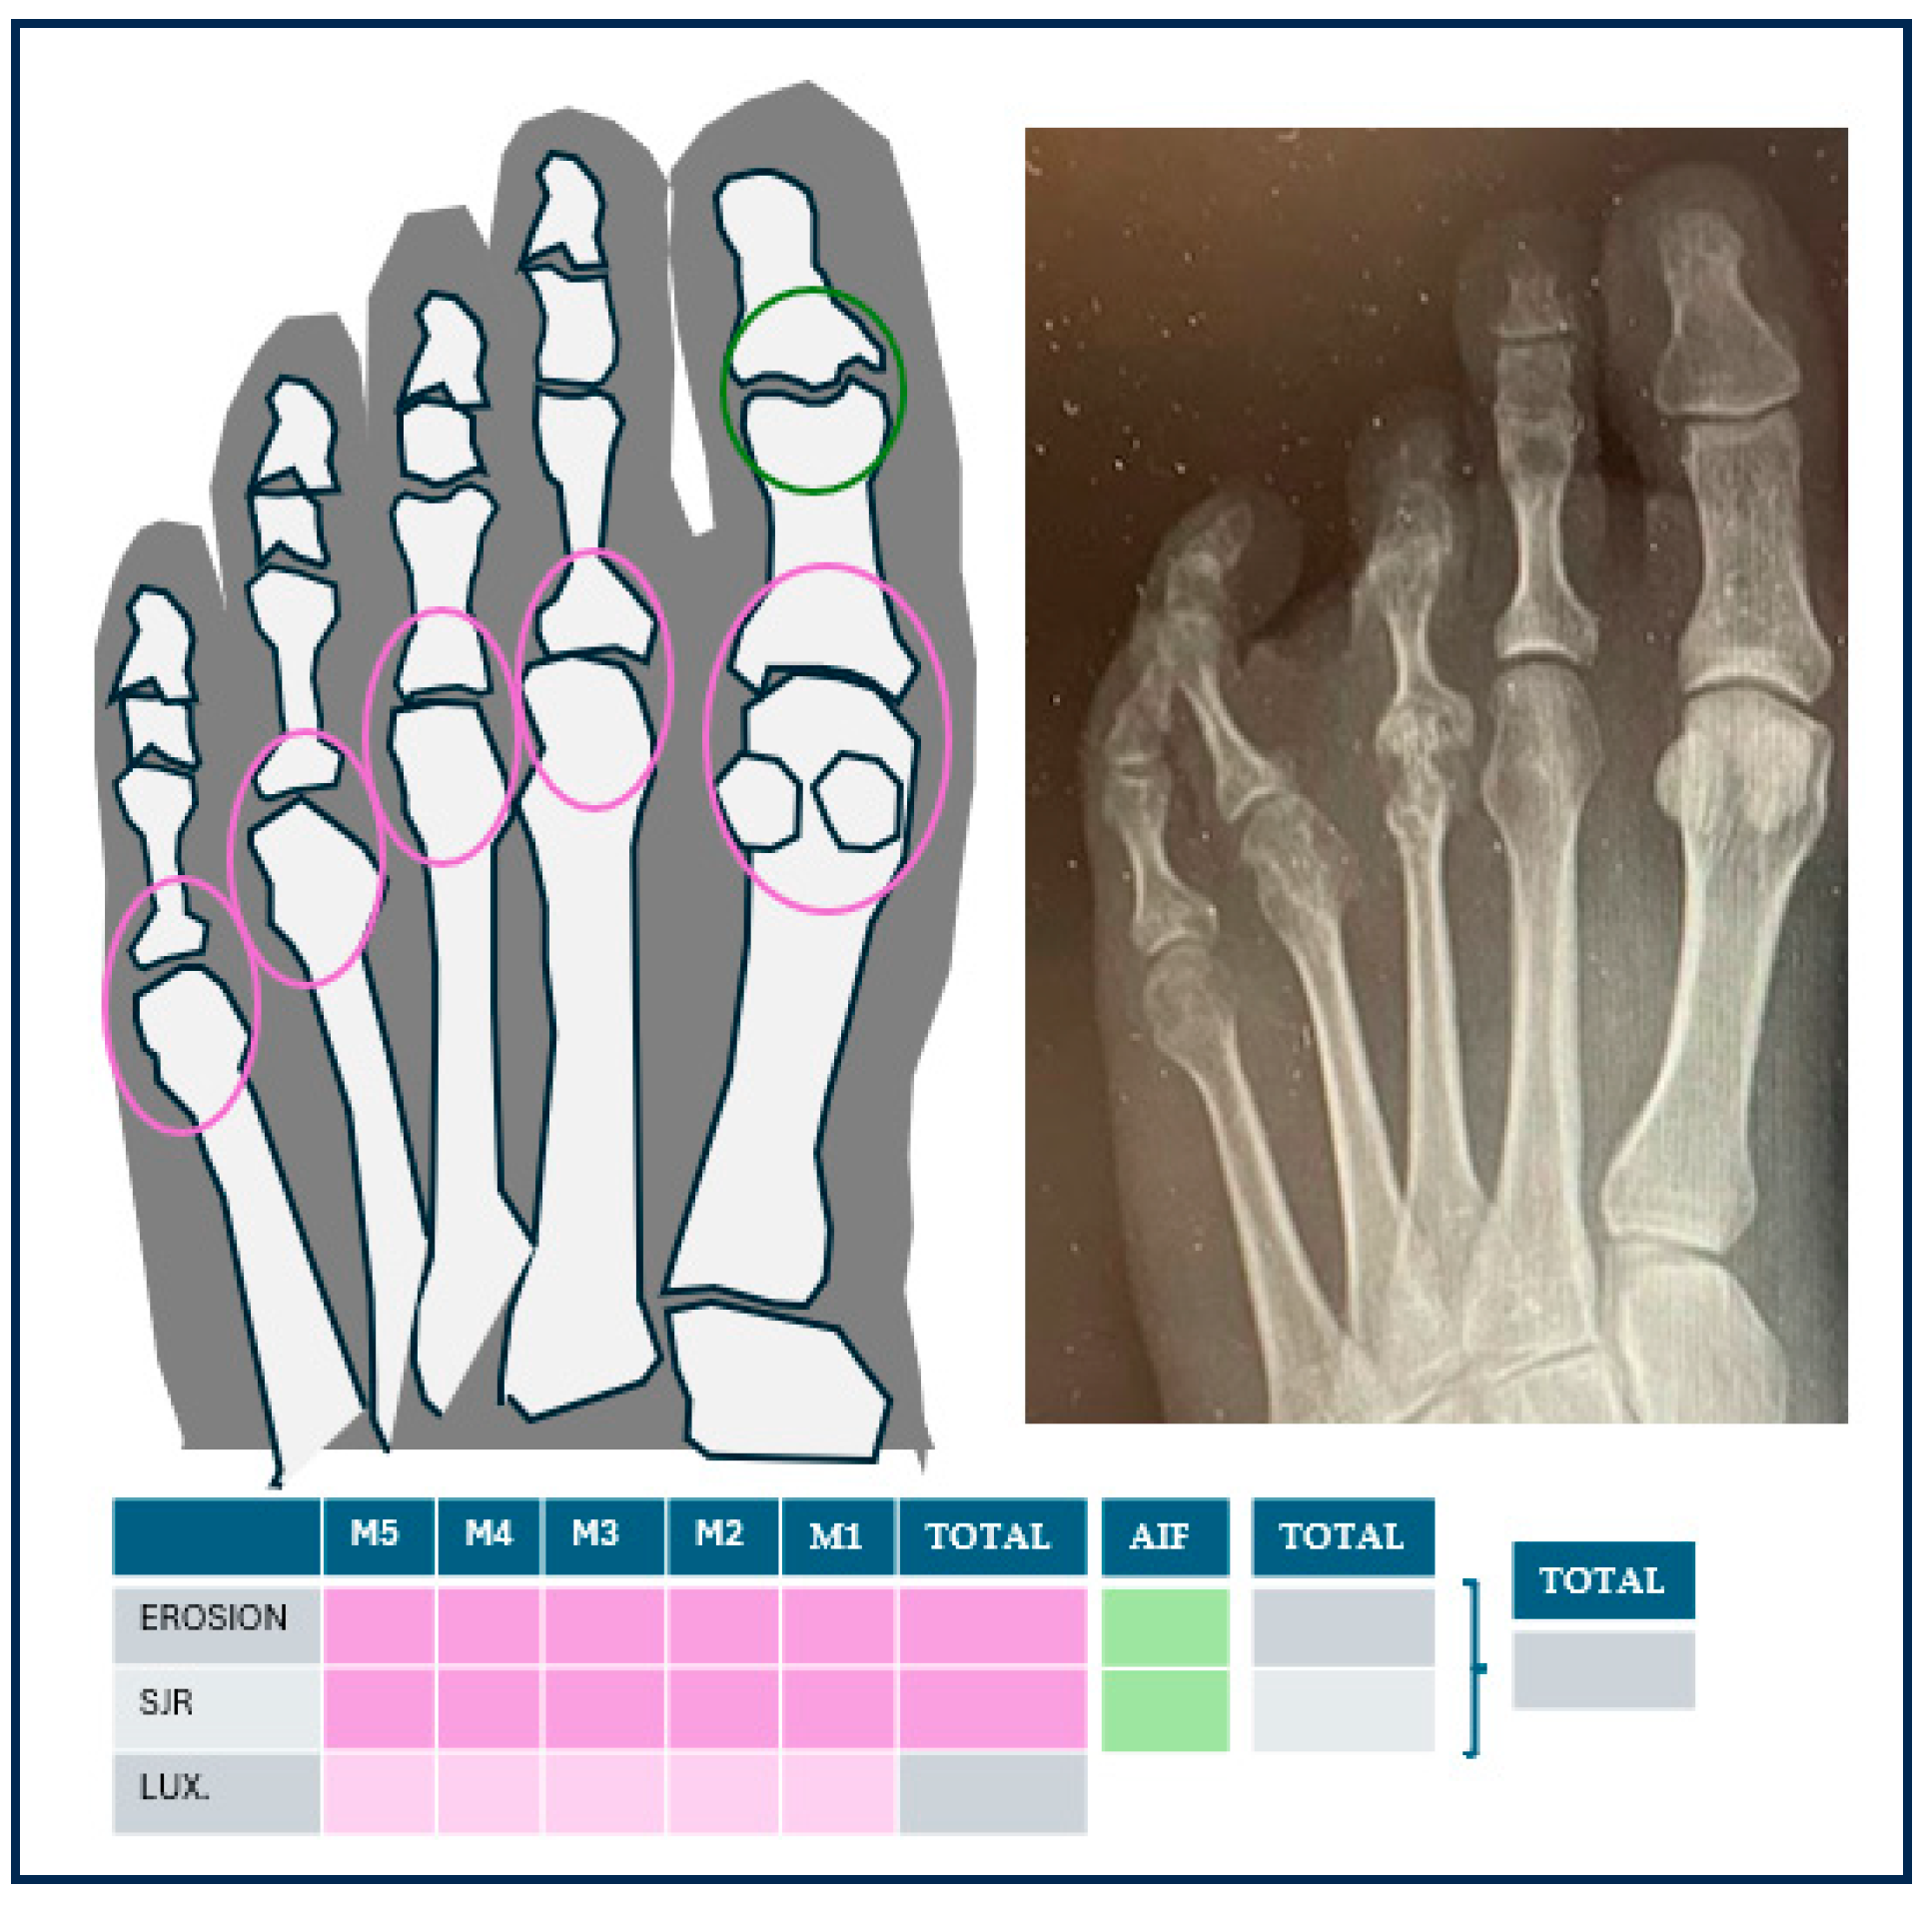

The radiological assessment was carried out by a researcher with a PhD in Podiatry who specialised in rheumatic foot. This researcher evaluated the anonymised X-ray in loading dorsoplantar projection, provided by the patient. The 5th MTPJ and the first interphalangeal joint (IPJ) of the hallux were analysed, which are included in the scales of radiological damage [65]. To evaluate the osteoarticular damage, the researcher gathered: the presence or absence of erosions and JSR, assigning one point to each joint in the case of presenting erosions (regardless of their magnitude) and one point in the case of JSR (regardless of their degree), and the total score in each joint was evaluated (with a maximum of 2 points). The scores of the 6 joints were gathered [65], with a maximum of 12 points per foot. Moreover, the total amount of affected lesser-toe MTPJ was calculated, and the researcher specifically evaluated the number of affected MTPJ from 2nd to 5th. Luxation/subluxation of the MTPJ was also evaluated, which were defined as the partial (subluxation) or contactless (luxation) displacement of joint surfaces [66], considering also their presence or absence in each of the MTPJ and the total score. Figure 4 shows an image of an X-ray of a patient with metatarsal pain and a diagnosis of AR, a figure indicating the joints evaluated and a table in which the findings on the X-ray were filled in.

Figure 4.

In the metatarsophalangeal joints (circled in pink) and the hallux interphalangeal joint (circled in green), the presence of erosions and decreased joint space were evaluated by summation. In addition, the presence of subluxation or dislocation of the metatarsophalangeal joints was indicated. On the right an example of a radiograph of a patient with rheumatoid arthritis.